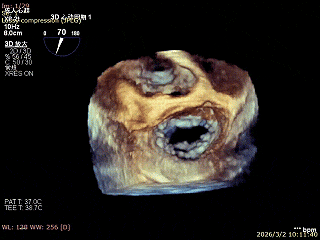

3D enface 切面

3D enface观察反流